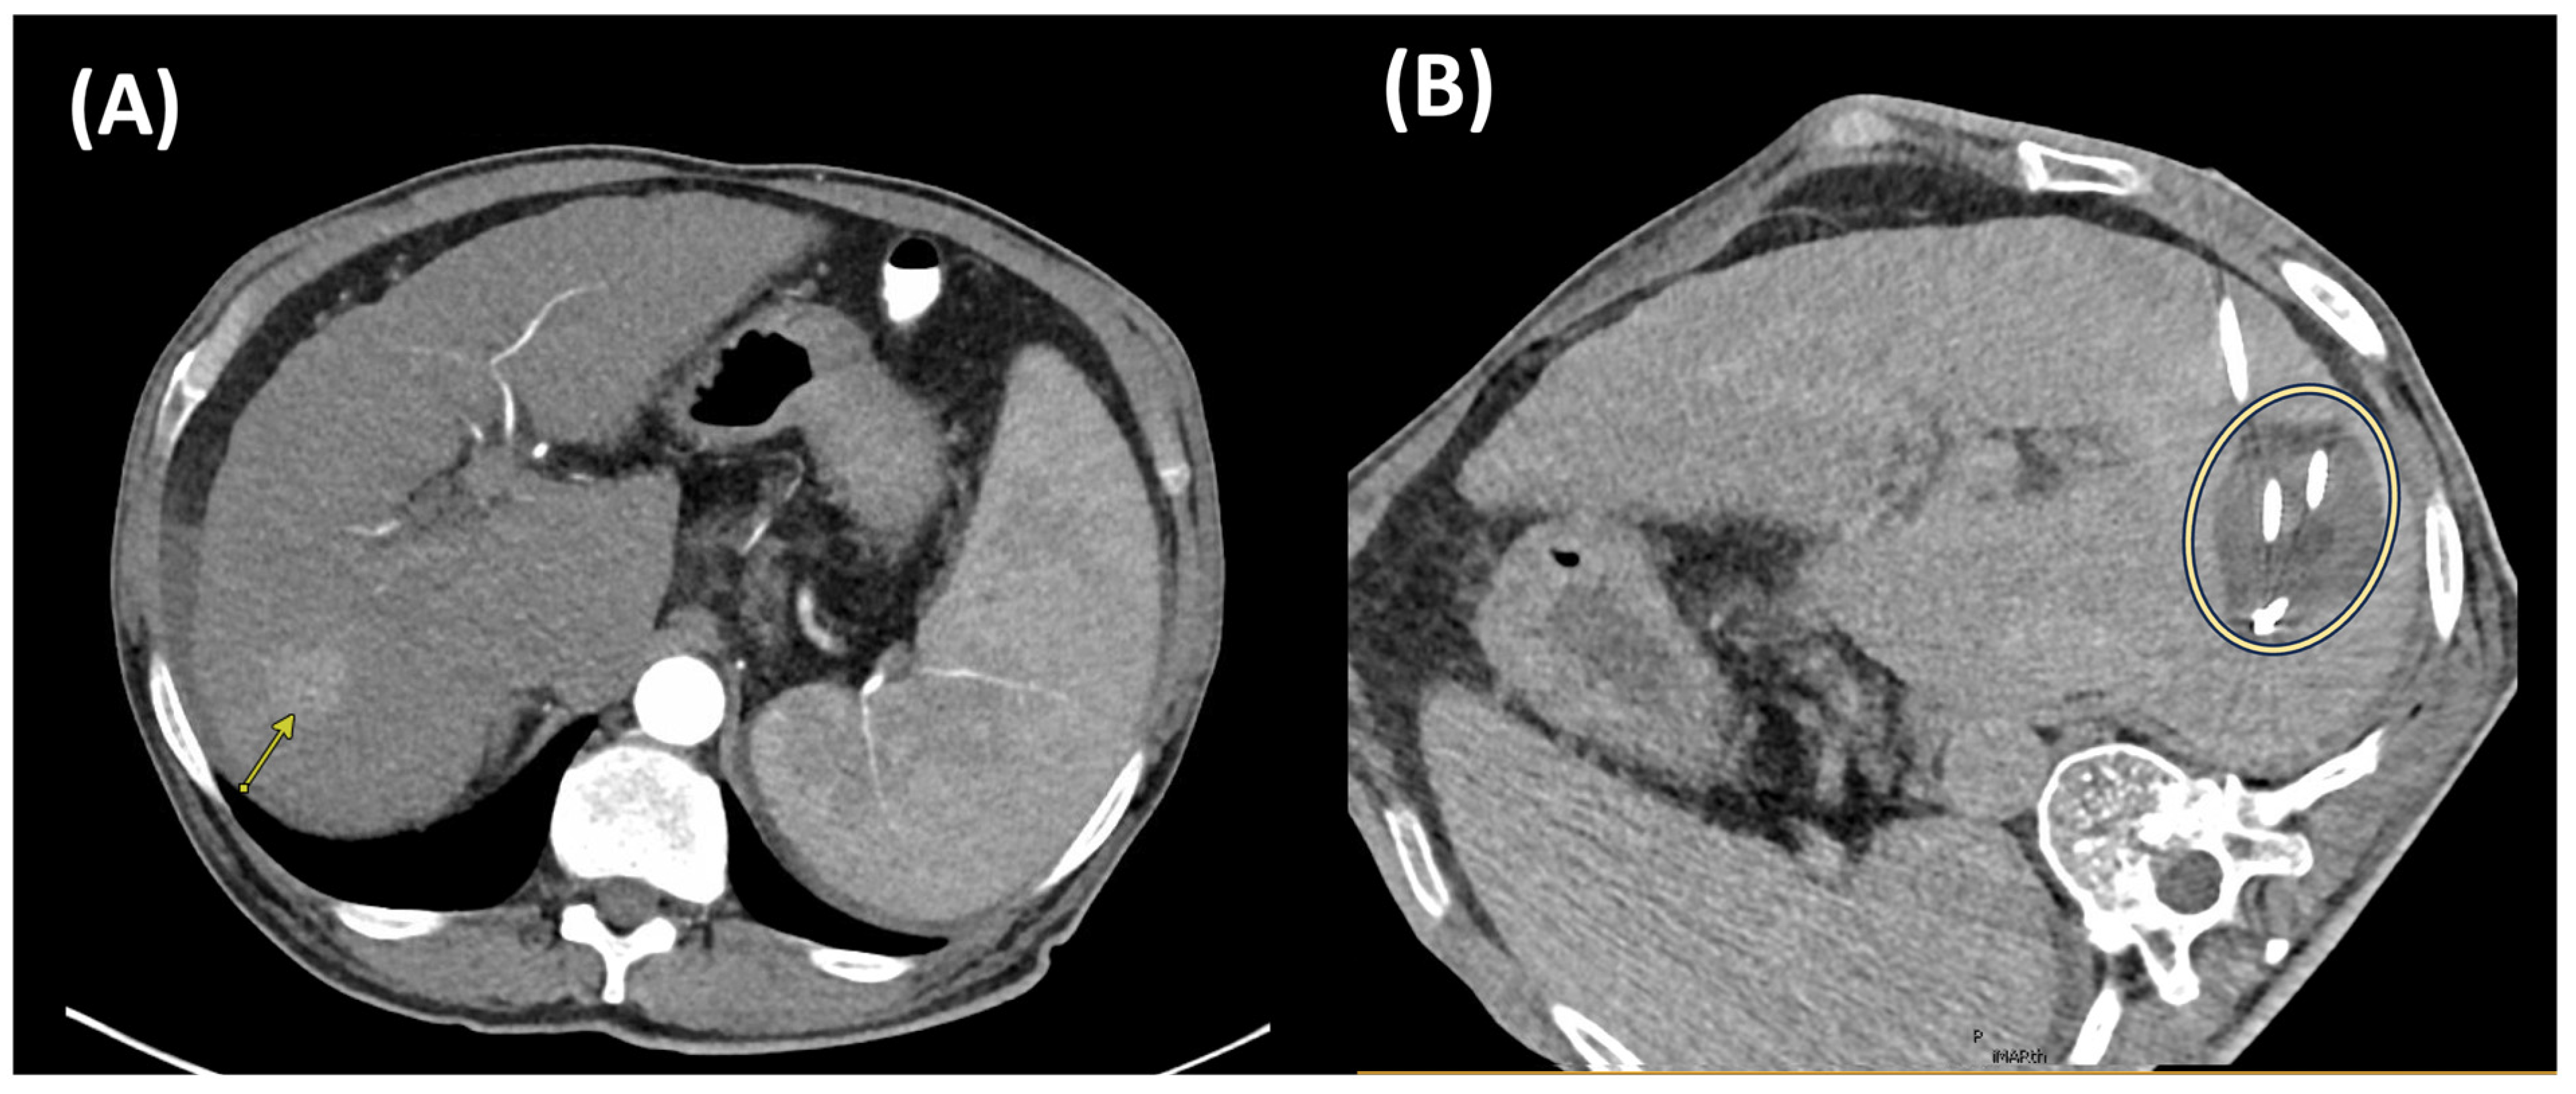

4.1. Trans-Arterial Radioembolization

4.2. External Beam Radiotherapy